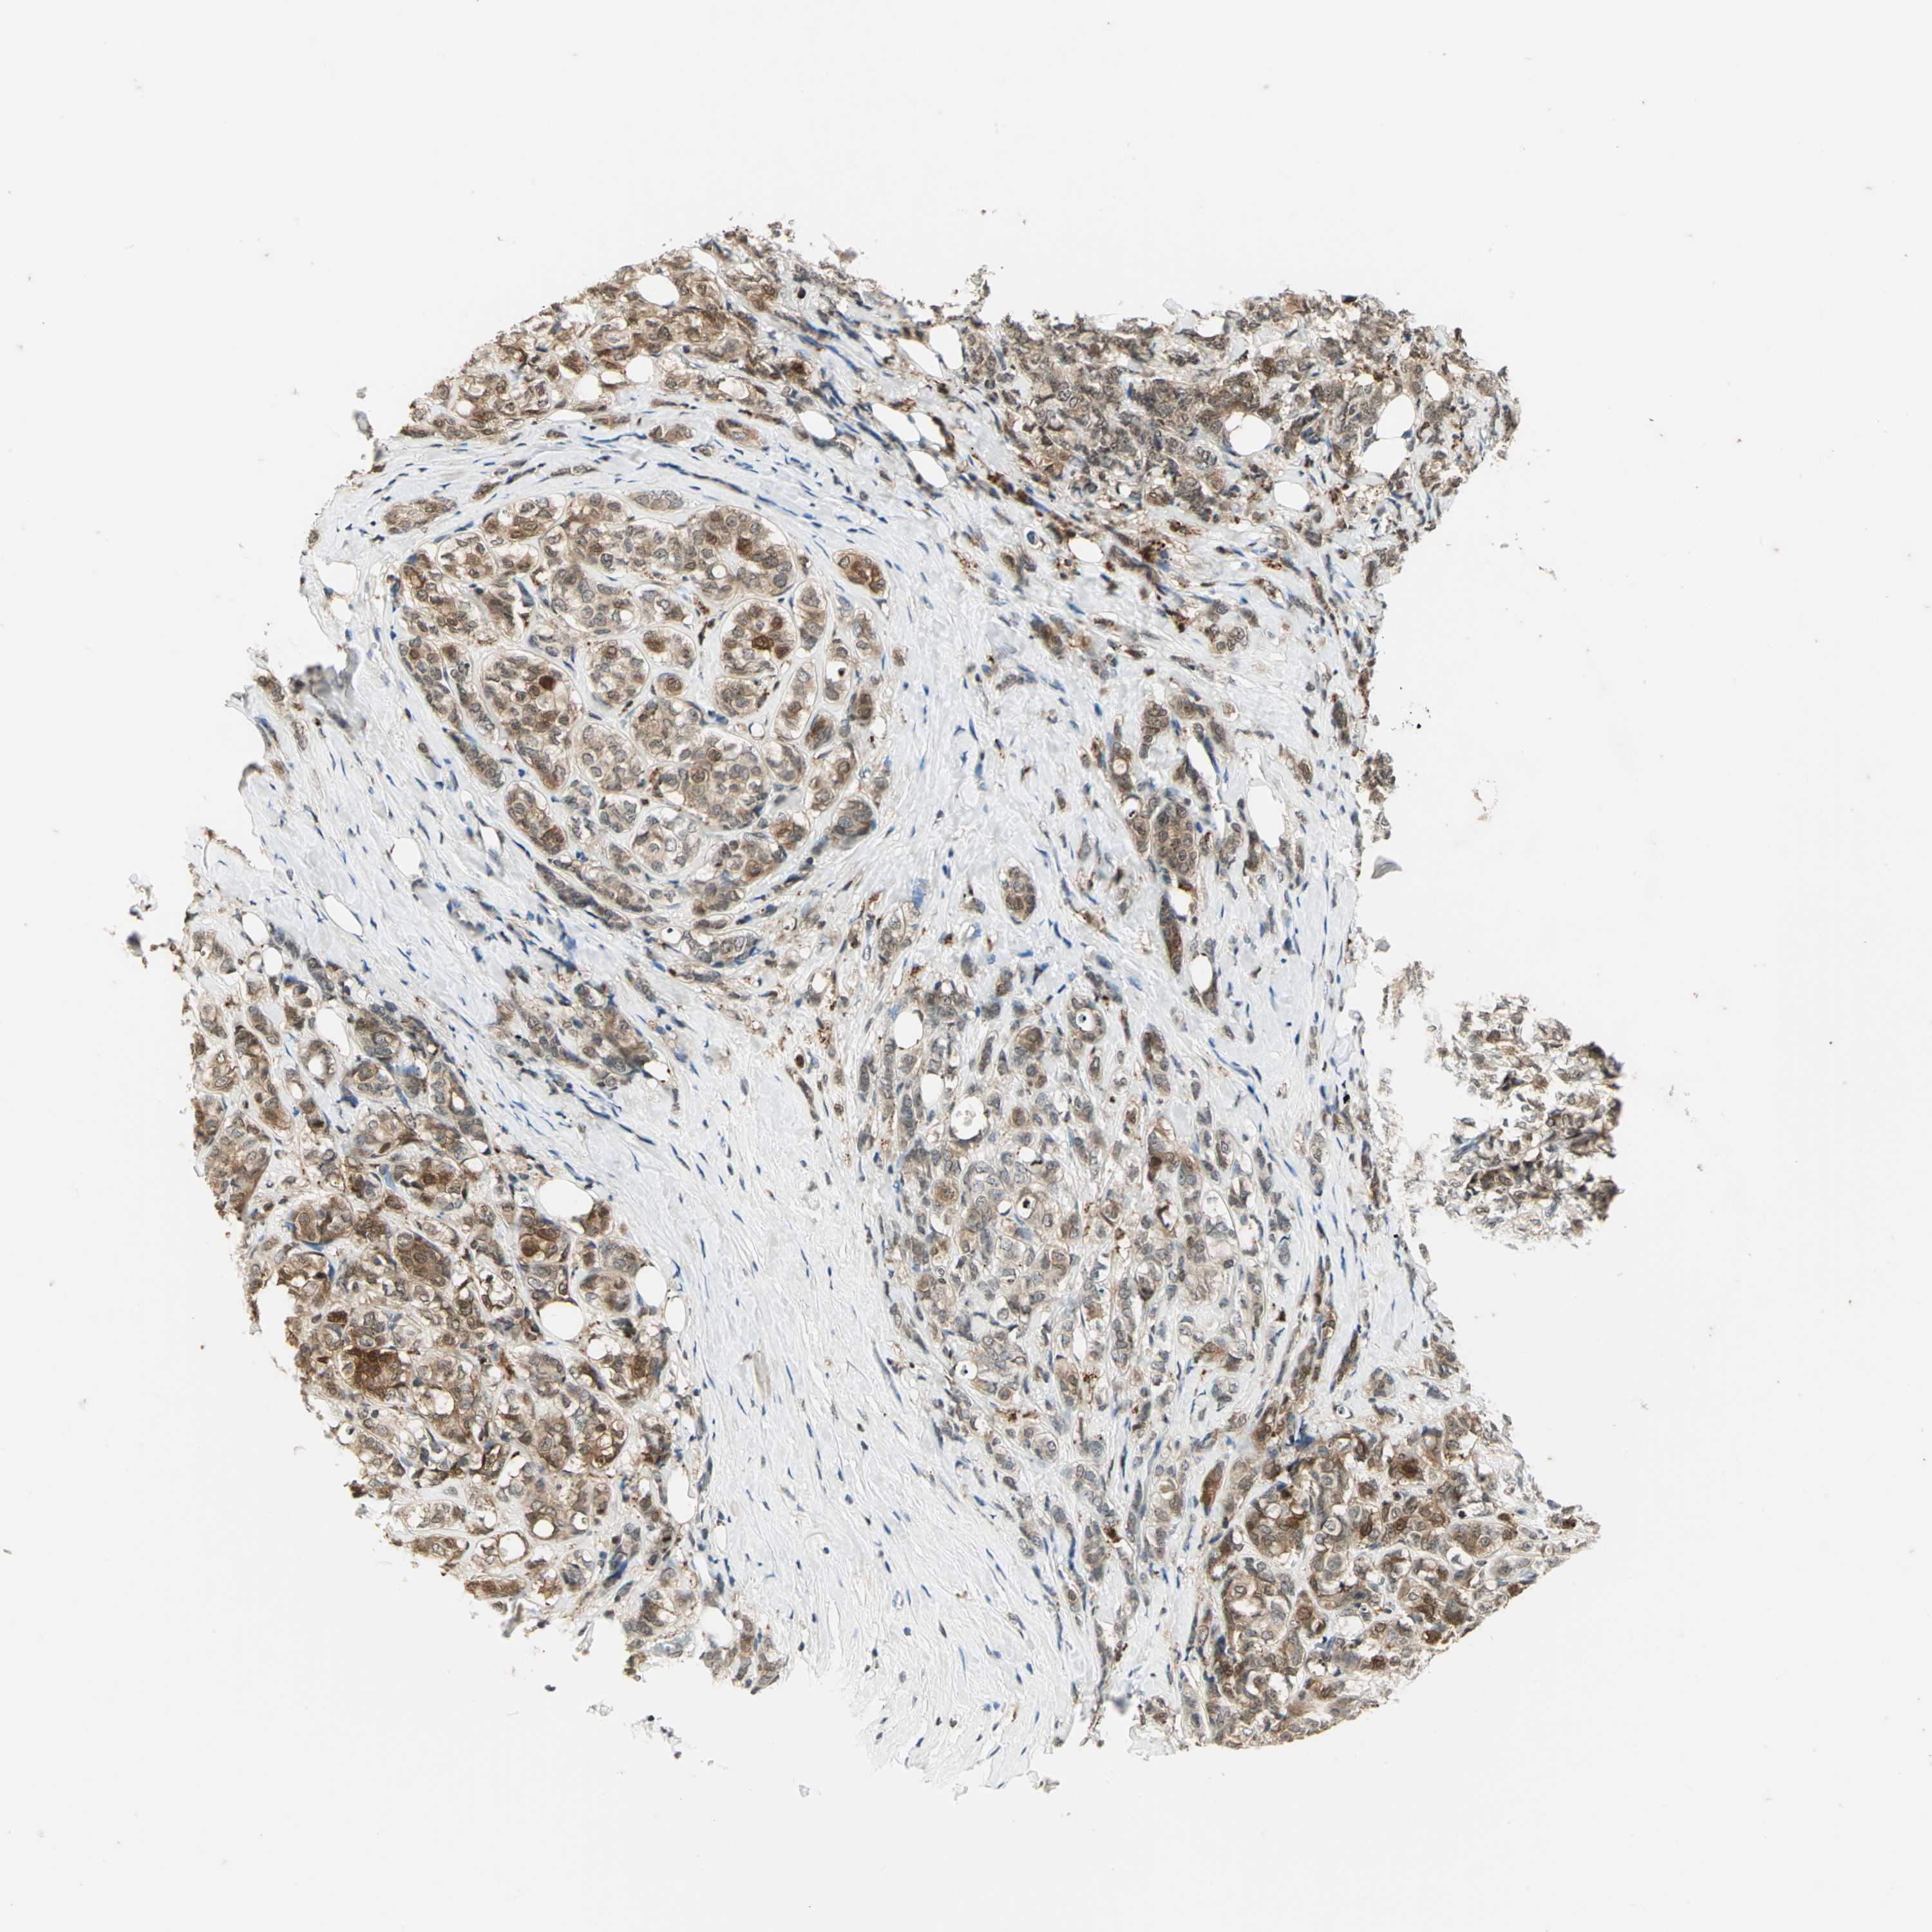

LGALS3

CANCER BREAST CANCER Show tissue menu

BRCA TCGA BRCA VALIDATION PROTEIN EXPRESSION

LGALS3 is not prognostic in Breast Invasive Carcinoma (TCGA)